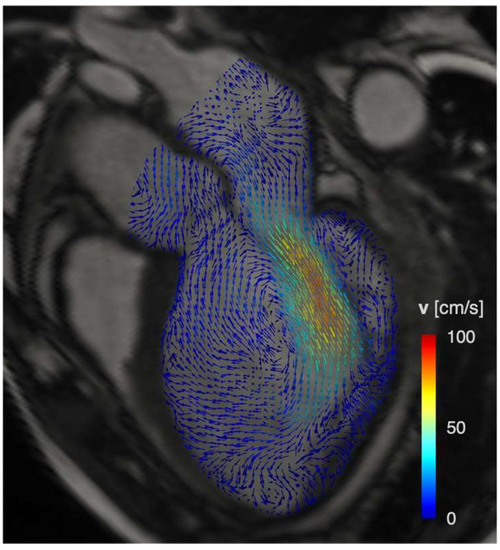

- Dyverfeldt, P.; Bissell, M.; Barker, A.J.; Bolger, A.F.; Carlhall, C.J.; Ebbers, T.; Francios, C.J.; Frydrychowicz, A.; Geiger, J.; Giese, D.; et al. 4D flow cardiovascular magnetic resonance consensus statement. J. Cardiovasc. Magn. Reson. 2015, 17, 72. [Google Scholar] [CrossRef]

- Eriksson, J.; Bolger, A.F.; Ebbers, T.; Carlhall, C.J. Four-dimensional blood flow-specific markers of LV dysfunction in dilated cardiomyopathy. Eur. Heart J. Cardiovasc. Imaging 2013, 14, 417–424. [Google Scholar] [CrossRef]

- Garg, P.; van der Geest, R.J.; Swoboda, P.P.; Crandon, S.; Fent, G.J.; Foley, J.R.J.; Dobson, L.E.; Al Musa, T.; Onciul, S.; Vijayan, S.; et al. Left ventricular thrombus formation in myocardial infarction is associated with altered left ventricular blood flow energetics. Eur. Heart J. Cardiovasc. Imaging 2019, 20, 108–117. [Google Scholar] [CrossRef] [PubMed]

- Kaur, H.; Assadi, H.; Alabed, S.; Cameron, D.; Vassiliou, V.S.; Westenberg, J.J.M.; van der Geest, R.; Zhong, L.; Dastidar, A.; Swift, A.J.; et al. Left Ventricular Blood Flow Kinetic Energy Assessment by 4D Flow Cardiovascular Magnetic Resonance: A Systematic Review of the Clinical Relevance. J. Cardiovasc. Dev. Dis. 2020, 7, 37. [Google Scholar] [CrossRef]

- Garg, P.; Crandon, S.; Swoboda, P.P.; Fent, G.J.; Foley, J.R.J.; Chew, P.G.; Brown, L.A.E.; Vijayan, S.; Hassell, M.; Nijveldt, R.; et al. Left ventricular blood flow kinetic energy after myocardial infarction—Insights from 4D flow cardiovascular magnetic resonance. J. Cardiovasc. Magn. Reson. 2018, 20, 61. [Google Scholar] [CrossRef]

- Riva, A.; Sturla, F.; Pica, S.; Camporeale, A.; Tondi, L.; Saitta, S.; Caimi, A.; Giese, D.; Palladini, G.; Milani, P.; et al. Comparison of Four-Dimensional Magnetic Resonance Imaging Analysis of Left Ventricular Fluid Dynamics and Energetics in Ischemic and Restrictive Cardiomyopathies. J. Magn. Reson. Imaging 2022, 56, 1157–1170. [Google Scholar] [CrossRef]

- Eriksson, J.; Zajac, J.; Alehagen, U.; Bolger, A.F.; Ebbers, T.; Carlhall, C.J. Left ventricular hemodynamic forces as a marker of mechanical dyssynchrony in heart failure patients with left bundle branch block. Sci. Rep. 2017, 7, 2971. [Google Scholar] [CrossRef] [PubMed]

- Eriksson, J.; Bolger, A.F.; Ebbers, T.; Carlhall, C.J. Assessment of left ventricular hemodynamic forces in healthy subjects and patients with dilated cardiomyopathy using 4D flow MRI. Physiol. Rep. 2016, 4, e12685. [Google Scholar] [CrossRef]

- Filomena, D.; Cimino, S.; Monosilio, S.; Galea, N.; Mancuso, G.; Francone, M.; Tonti, G.; Pedrizzetti, G.; Maestrini, V.; Fedele, F.; et al. Impact of intraventricular haemodynamic forces misalignment on left ventricular remodelling after myocardial infarction. ESC Heart Fail. 2022, 9, 496–505. [Google Scholar] [CrossRef]